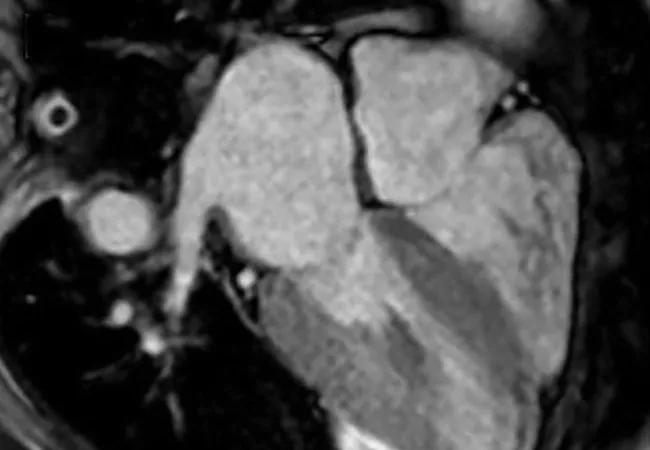

Advanced Noninvasive Tools for the Diagnosis of Cardiac Amyloidosis: What’s Their Role?

A 48-year-old female was transferred to Cleveland Clinic from an outside hospital for a heart transplantation workup due to severe heart failure. She had been diagnosed with amyloidosis at age 45 and had experienced severe shortness of breath, particularly with minimal exertion. Upon her arrival, the Cleveland Clinic Amyloidosis Center team promptly initiated her on chemotherapy with the standard of care at the time, bortezomib, cyclophosphamide and dexamethasone (CyBorD). She was hospitalized for two weeks before being discharged on the therapy.